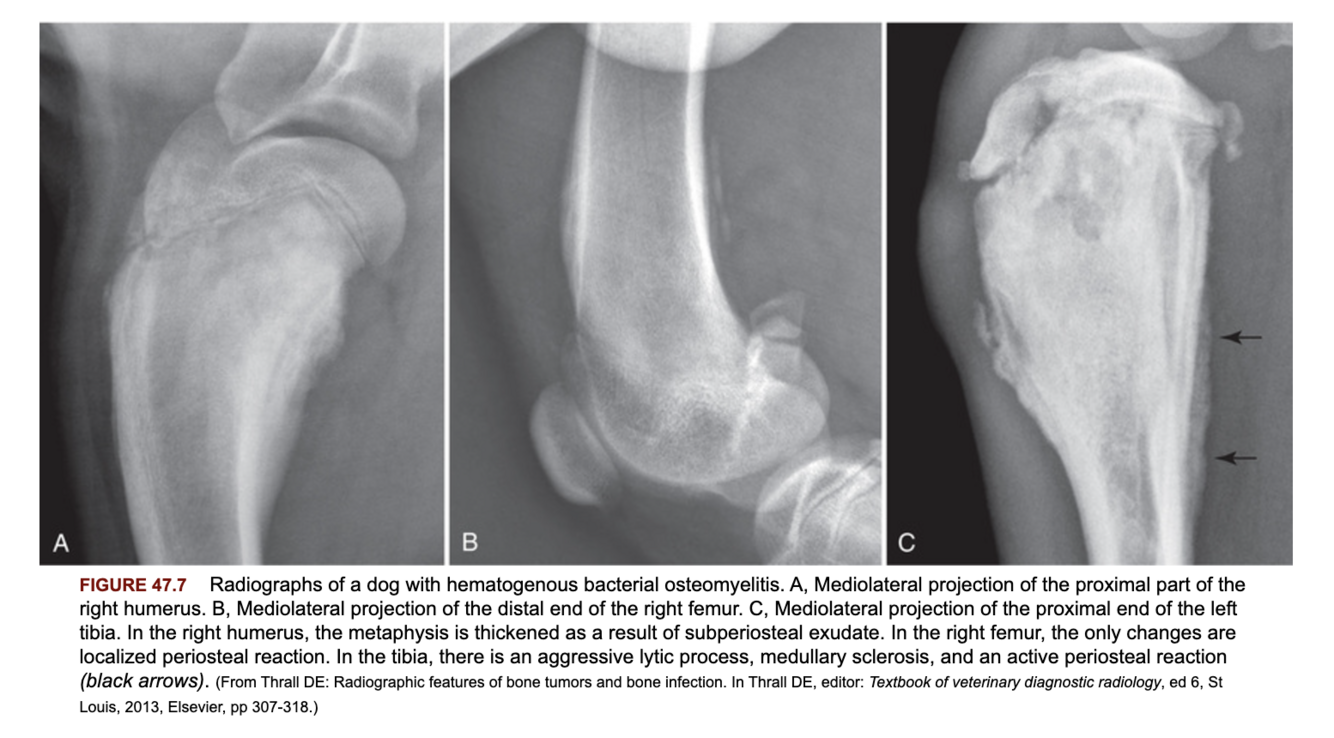

What are some radiographic changes associated with hematogenous osteomyelitis?

A

Polyostic lesions in the metaphysis of long bones +/- those signs seen for posttraumatic osteomyelitis. Typically do not extend into the adjacent joint.

What is the most common location of hematogenous osteomyelitis?

Metaphyseal regions of the bone. Potential reasons include capillaries lacking a basement membrane, sluggish blood flow +/- minor trauma.